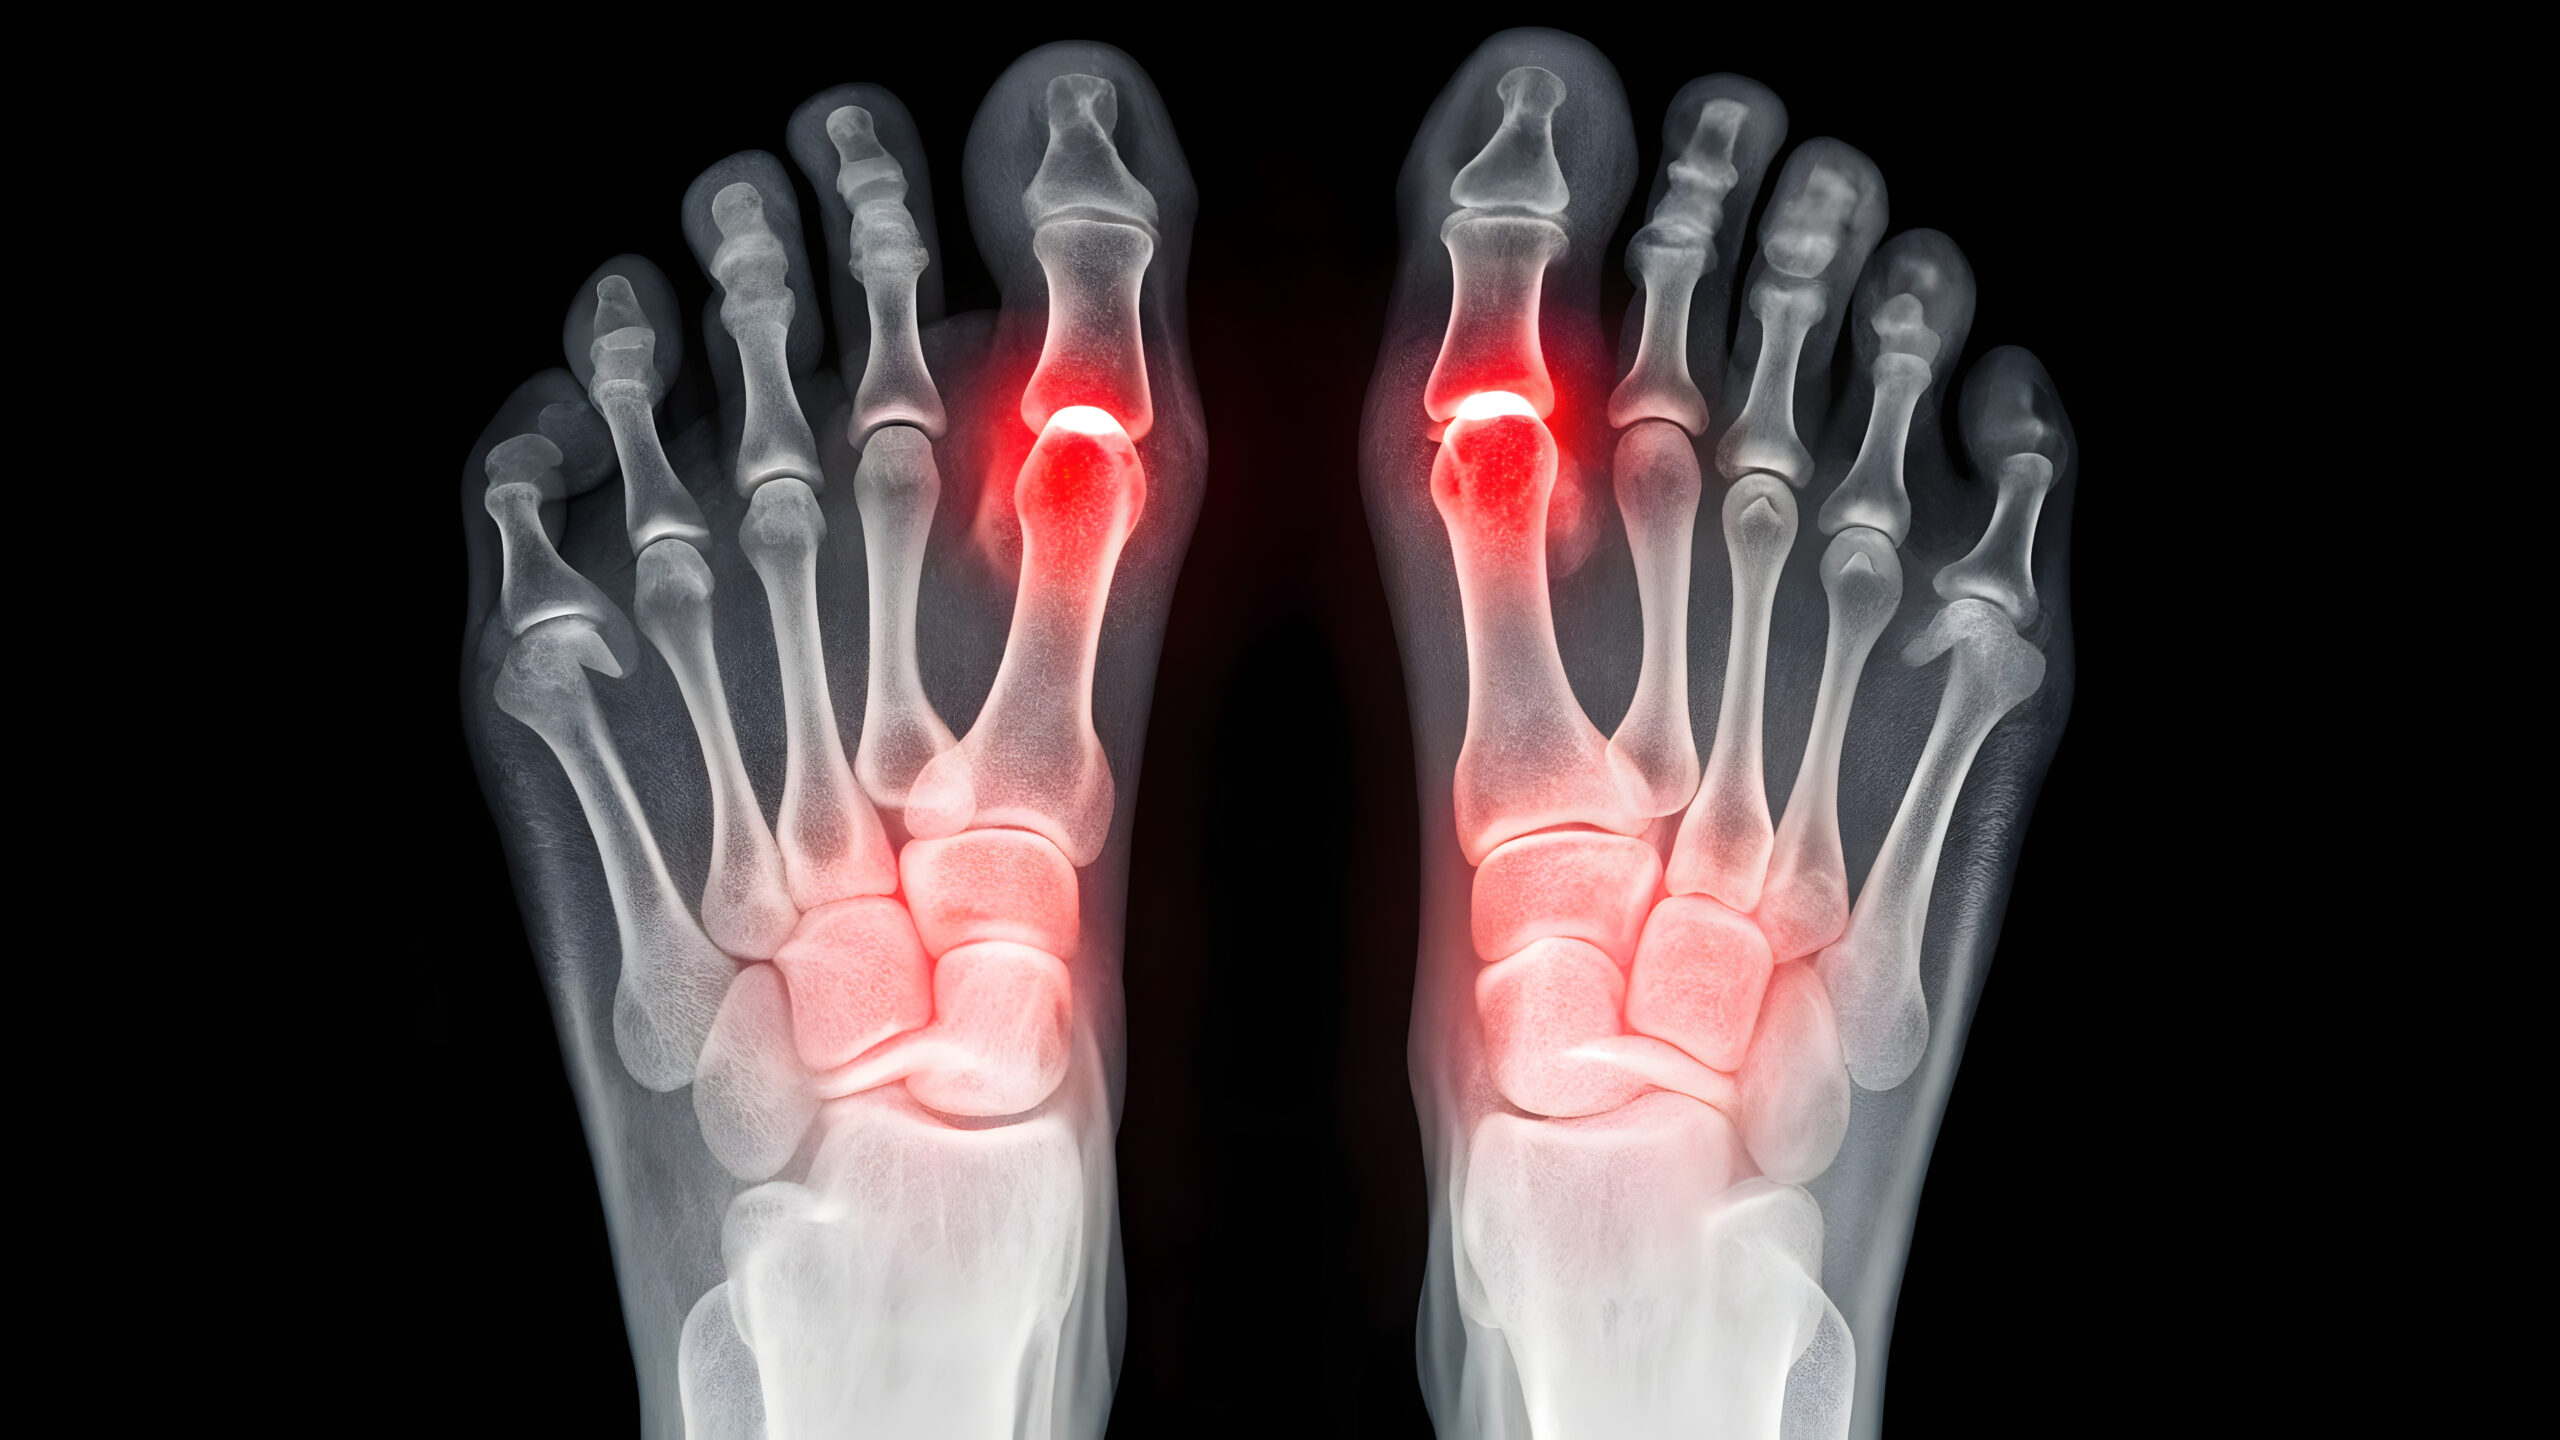

The Cartiva Toe Implant Lawsuit involves claims that the Cartiva Synthetic Cartilage Implant (SCI) was defectively designed and manufactured. This device was intended to treat arthritis of the big toe joint. However, many patients experienced serious complications and early implant failure.

Although the implant was marketed as a motion-preserving alternative to toe fusion, many patients report different outcomes. In fact, physicians and patients have documented failure rates far higher than those disclosed in clinical trials.

Additionally, the polyvinyl alcohol hydrogel material, designed to mimic natural cartilage, has shown significant problems. These problems include subsidence, bone loss, and chronic pain. As a result, many patients did not achieve long-term joint preservation.